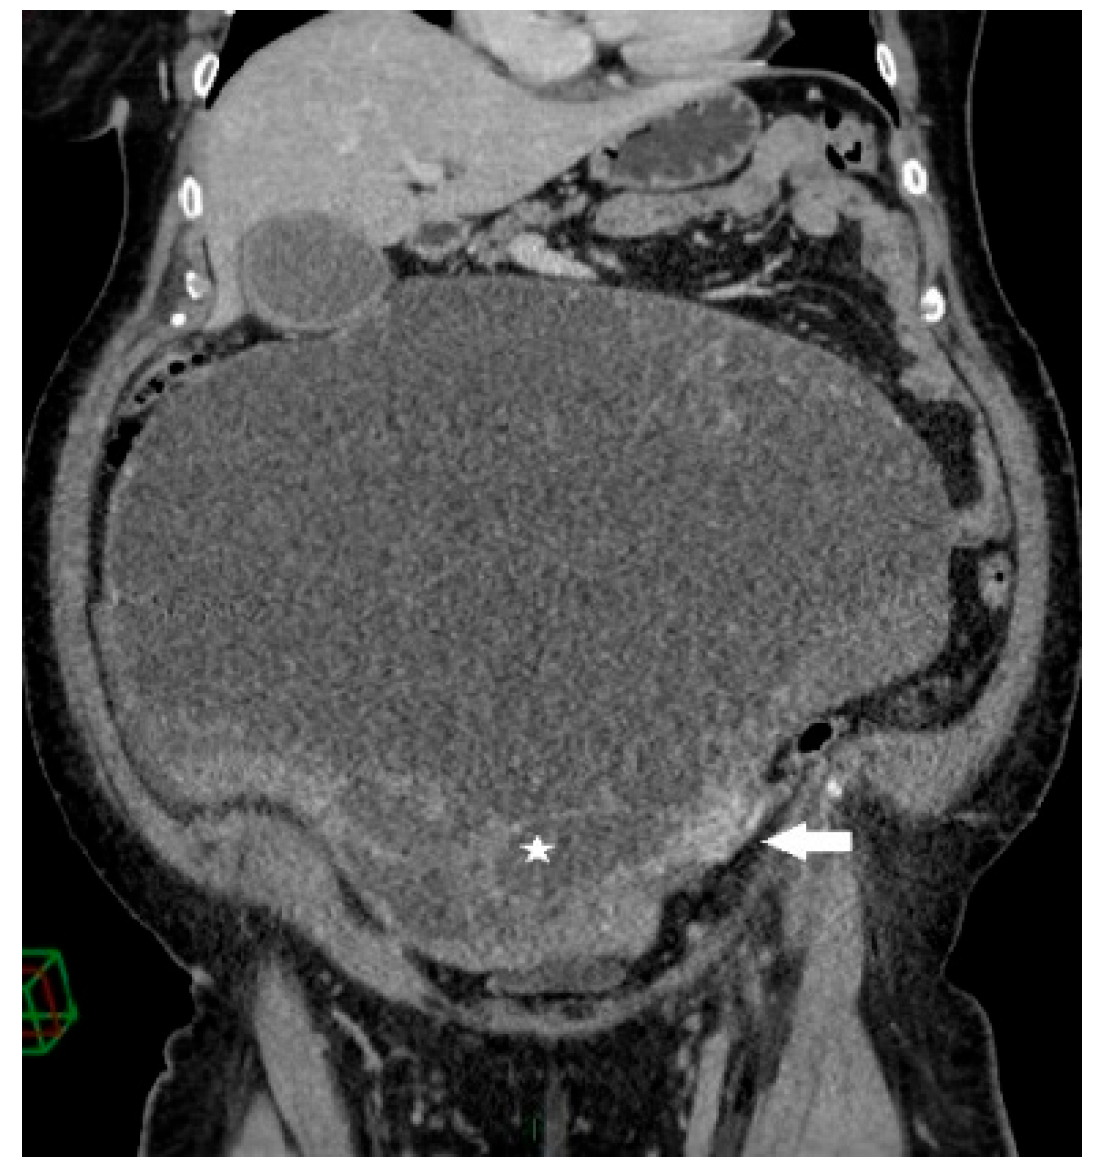

A 68-year-old female patient was admitted to our department due to increasing symptoms of abdominal bloating over the past four months. Other symptoms associated with ovarian cancer were denied by the patient. The patient’s medical history included surgery due to a rupture of an ovarian cyst, while a right adnexectomy was performed 43 years ago. Further, she had hypertension and glaucoma after antihypertensive therapy (Presolol, Asupt, Xalacon). Preoperative CT examination of the abdomen and pelvis confirmed the presence of a tumor in the abdomen and pelvis with a diameter of 335 mm × 275 mm × 345 mm. According to the CT features, the tumor was displacing the surrounding structures, albeit without signs of their infiltration. Initially, the tumor corresponded to left ovarian cystadenocarcinoma (Figure 1, Figure 2 and Figure 3). No intraluminal pathological changes were detected during upper flexible endoscopy and colonoscopy.

Figure 2.

Coronal contrast-enhanced CT image shows a giant predominantly cystic mass with innumerable tiny locules (white star) of variable attenuation arising from the left ovary, which is surrounded by dilated periovarian veins (white arrow).